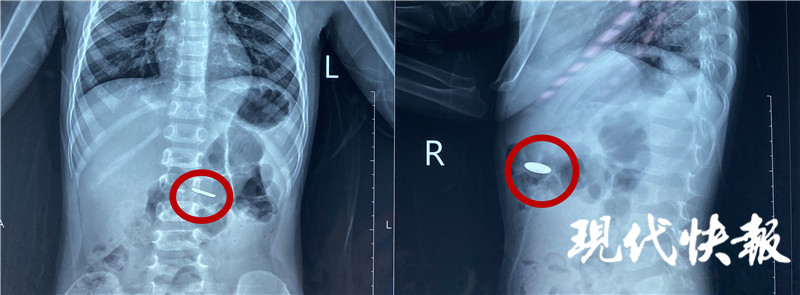

4月20日,江蘇淮安,小豪的家人在收納玩具的時候,發(fā)現常用的遙控器里的一顆紐扣電池不見了,家人的第一反應是電池被小豪吃了,趕緊帶著他前往醫(yī)院。經過緊張的手術,醫(yī)生從2歲男童小豪(化名)的小腸內取出一枚紐扣電池,電池周圍的腸壁被腐蝕發(fā)黑。

“當時拍了片子發(fā)現電池在胃部,消化內科的醫(yī)生及時給他做了胃鏡檢查,這個電池比較小,已經快速排空進入了小腸,胃鏡沒有發(fā)現電池。后來又拍片檢查,確認電池已經進入小腸,就轉入外科進行手術治療。”淮安市婦幼保健院小兒外科主治醫(yī)師顧春暉說。

完善手術準備,醫(yī)生通過腹腔鏡將電池取出。“這個手術本身比較困難,因為這個電池非常薄,直徑只有1厘米左右,小腸非常長,我們用了很長時間才找到這個電池,電池附近的腸道黏膜已經發(fā)黑,形成了化學性的腐蝕,如果時間再長一點可能造成穿孔等一些非常嚴重的后果。”顧春暉說。